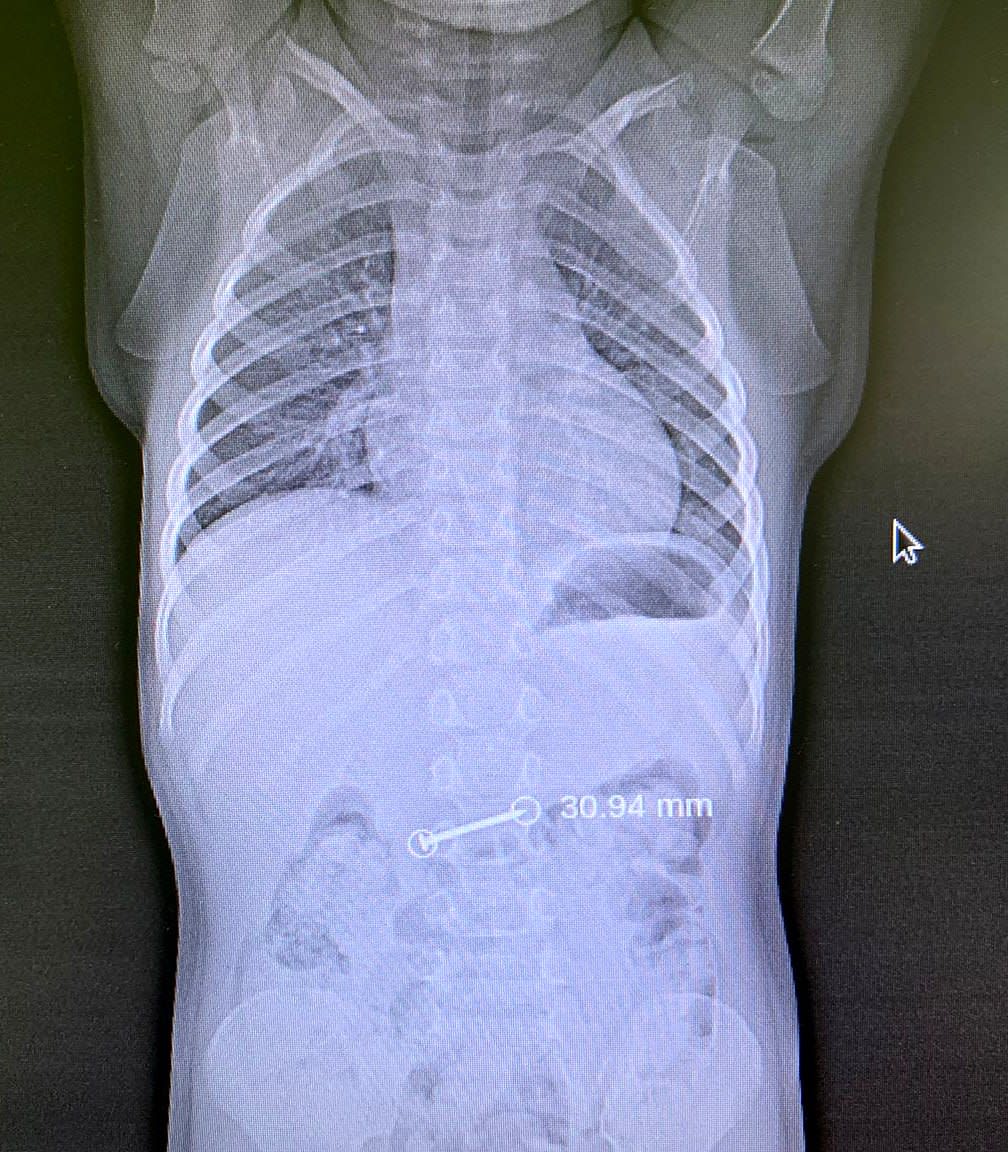

В воскресенье врачи отделения эндоскопии буквально догоняли «ускользающий» гвоздь. 3-хлетняя девочка держала его во рту и случайно проглотила. На снимке инородное тело визуализировалось еще в желудке, однако во время проведения эзофагогастродуоденоскопии под наркозом там его уже не оказалось.

– При входе в 12-перстную кишку мы увидели острый конец гвоздя, стремящийся спуститься в нижележащие отделы желудочно-кишечного тракта, – рассказал врач отделения эндоскопии Михаил Николаевич Мочалов. – Подхватив зажимом самый кончик, мы аккуратно, не торопясь, вытащили инородное тело.